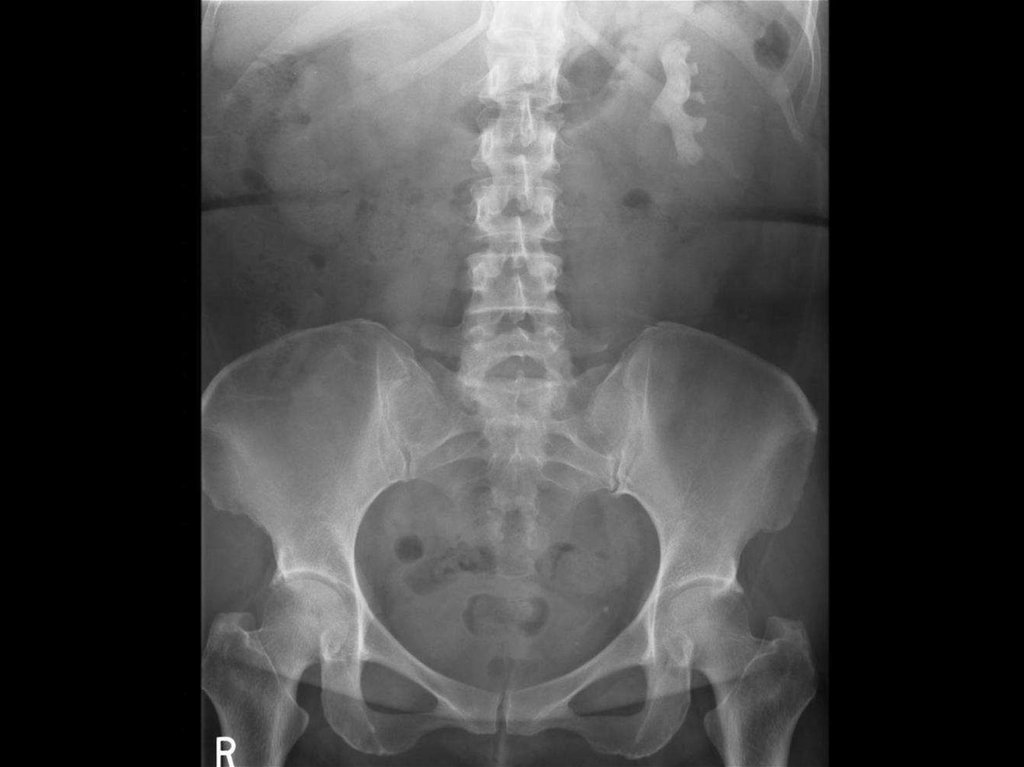

ОБЗОРНАЯ РЕНТГЕНОГРАФИЯ

Рентгенологическое исследование проводится

в условиях естественной контрастности.

Его основной целью является получение

изображения почек и обнаружение в зоне

мочевых органов различных патологических

включений - конкрементов, обызвествлений,

инородных тел.

Нативное исследование включает в себя

прежде всего обязательное выполнение

стандартной

обзорной

рентгенограммы

области мочевых органов в положении

больного лежа на спине.

Обзорная нативная рентгенография должна

обязательно предшествовать каждому рентгеноконтрастному исследованию, без этого

невозможен достоверный анализ их данных.

На рентгенограмме могут

определяться дополнительные

образования

высокой интенсивности в проекции

почечных лоханок, мочеточников,

мочевого пузыря которые, как правило,

обусловлены конкрементами.